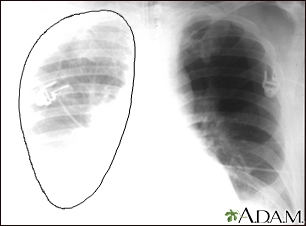

Aortic rupture - chest x-ray